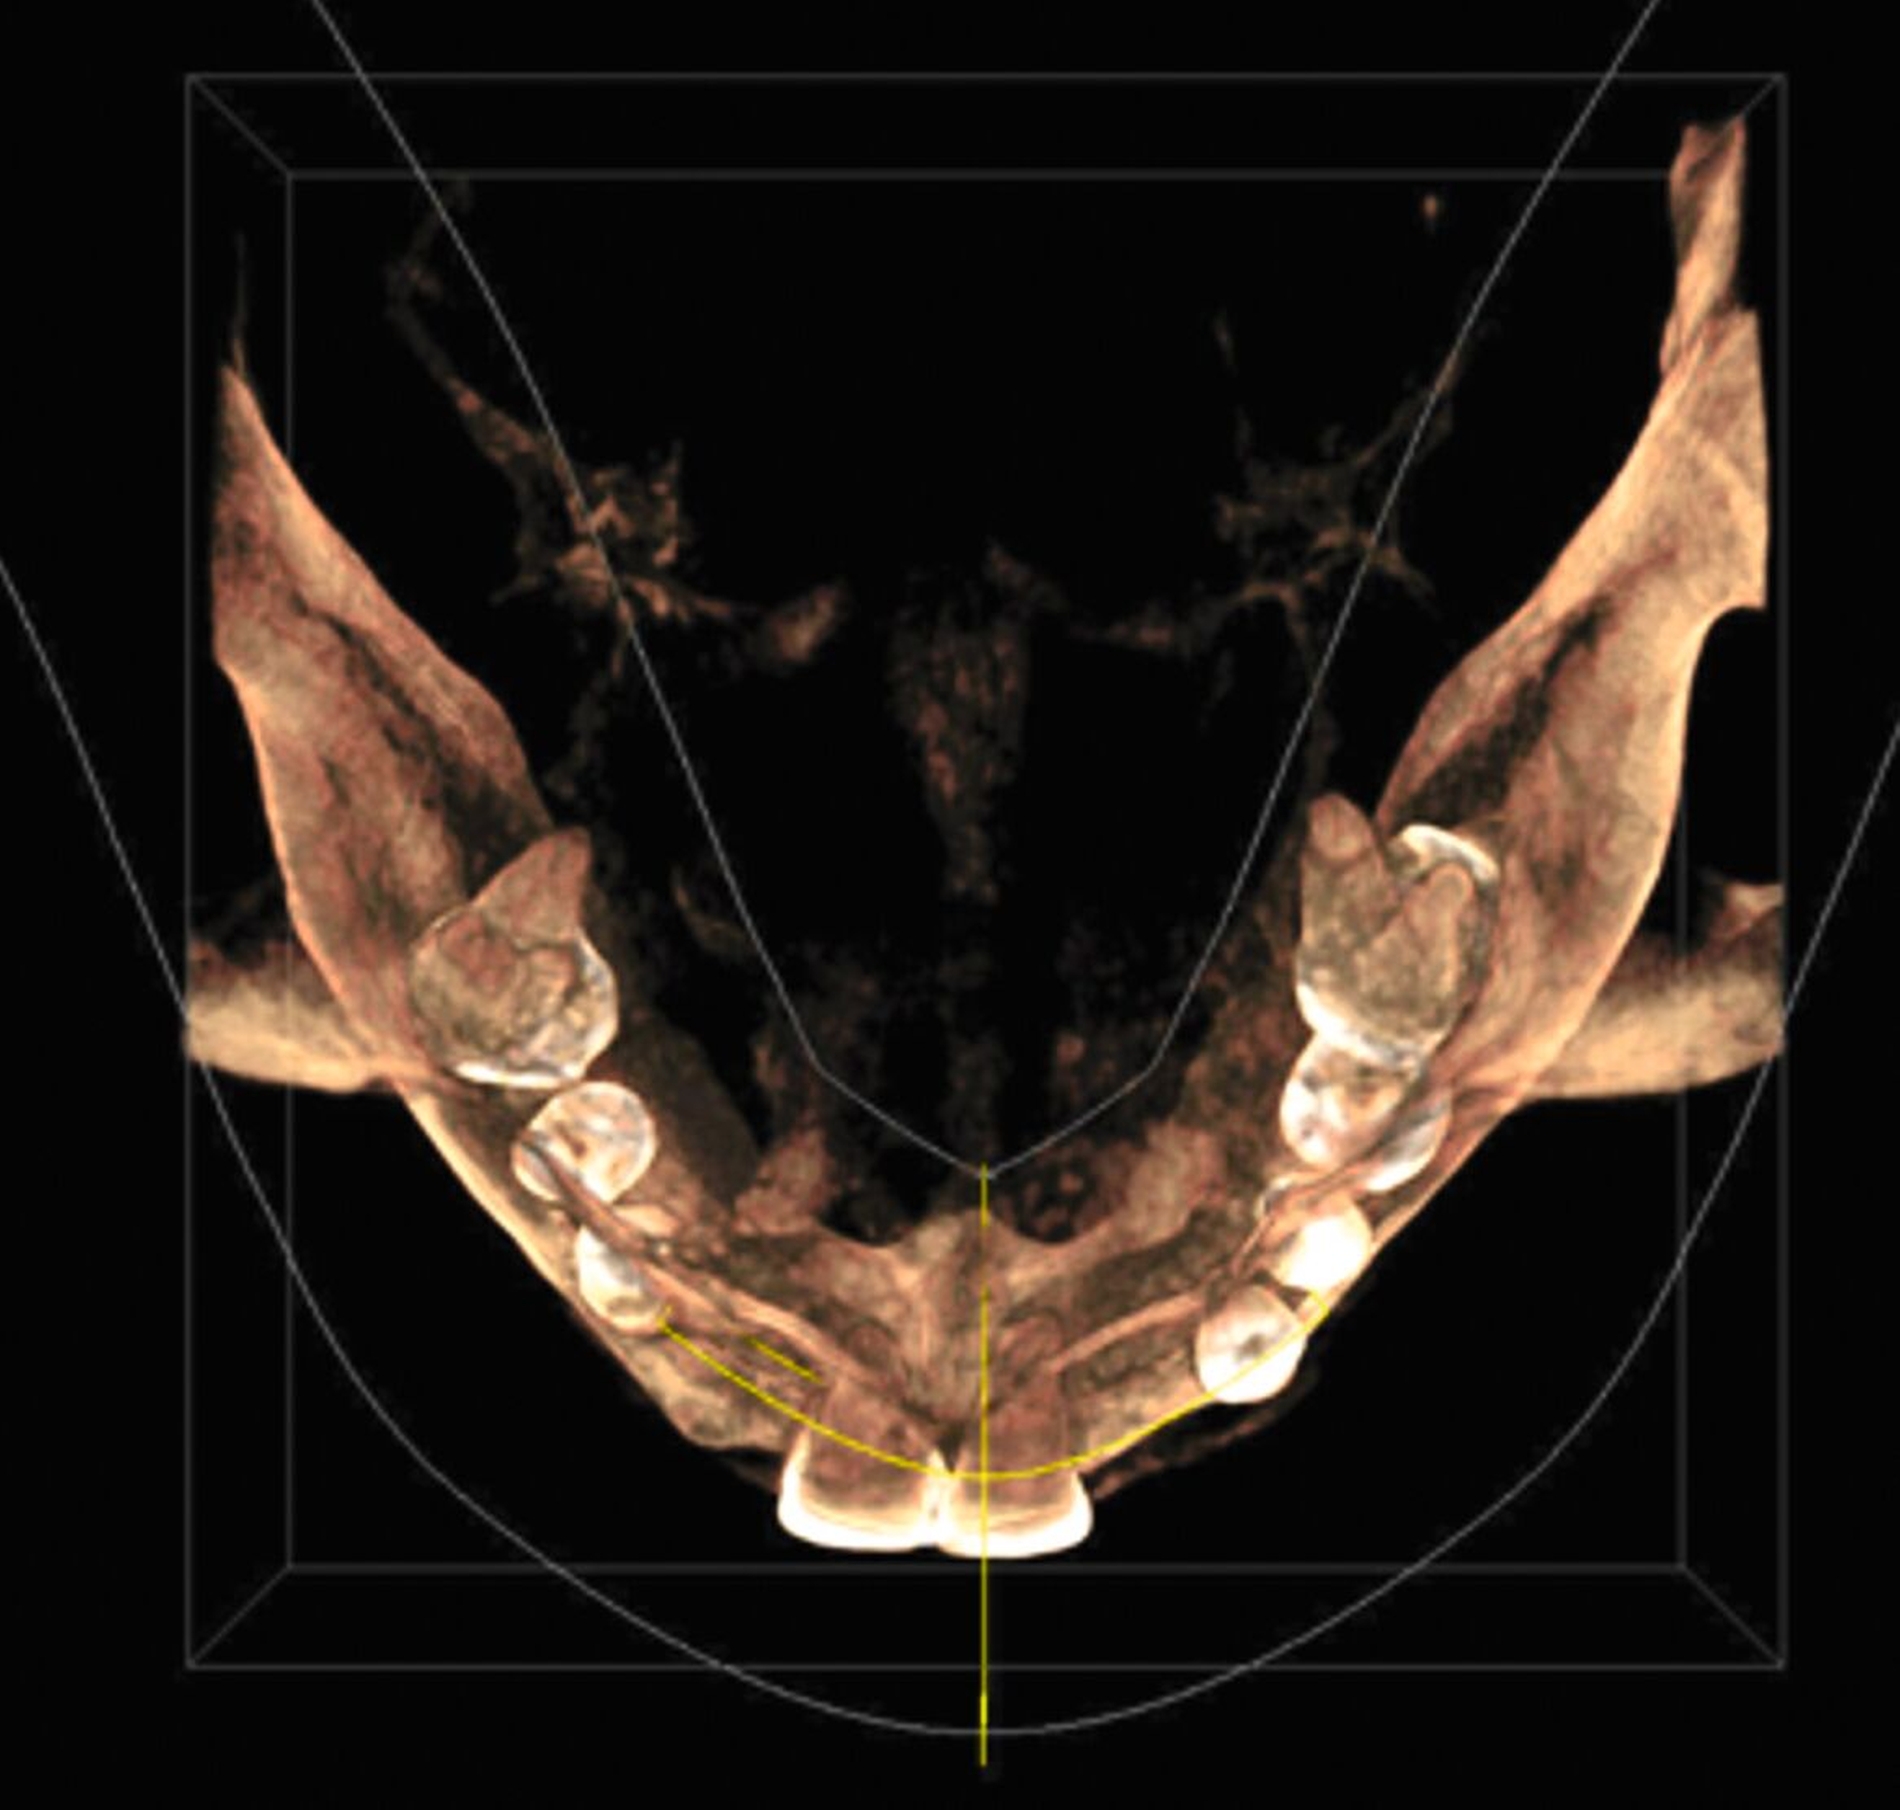

Zur Implantationsplanung wurden nach Abschluss der Vorbehandlungen und Prophylaxemaßnahmen zunächst eine digitale Volumentomografie (DVT) sowie aktuelle Situationsmodelle von Ober- und Unterkiefer zur Beurteilung der ossären Ausgangssituation erstellt. Es folgte die digitale Planung der Implantationen an den Regionen 12, 13, 13, 22, 23, 25, 33 und 43 (CoDiagnostiX Dental Wings, Straumann, Basel, Schweiz) sowie die Übertragung der dreidimensional geplanten Implantationen in gedruckte Bohrschablonen und die Festlegung von Art und Zeitpunkt erforderlicher Augmentationen (Abbildung 5).